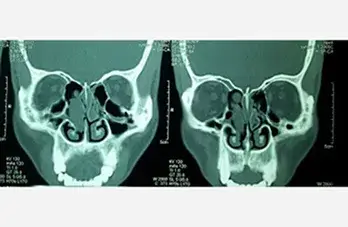

Haller Cell

Inverted Papilloma Nose

• Endoscopic Sinus Surgery

• Diagnostic Nasal Endoscopy